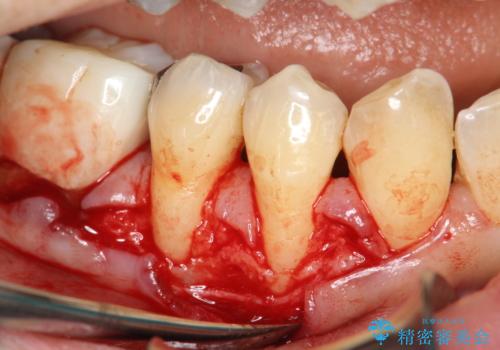

- 右下4番と5番に丈夫な歯肉が不足しているために、徐々に歯肉が下がってきていたケースです。

これ以上の歯肉退縮を防ぐべく、丈夫な歯肉の獲得を目的として結合組織移植術による対応を行いました。

患部にはごくわずかに丈夫な歯肉(角化歯肉)がある状態でした。この丈夫な歯肉の幅を十分に増大させ、厚みを持たせる事で、ブラッシングによっても下がりにくく安定した状態となります。

術式は歯冠側移動術と歯肉結合組織移植術を併用しました。

今回のケースでは小臼歯2本分の幅に渡って丈夫な歯肉を確保させるため、オペのデザイン上、横に幅広く均一な結合組織を採取する必要がありました。そのため、トラップドア方式で内部の組織をえぐって採取する術式は使わず、上顎歯肉の表層から結合組織部までを含む部分までを遊離歯肉採取の要領でやや深めに採取し、表層部分をトリミングする事で均一な厚みの結合組織を採取しました。この術式の利点として、上顎の歯肉に過度に深い侵襲を与える事がないため、組織採取部の術後の治癒が非常に早く、術後の不快症状も少なくて済む事が挙げられます。